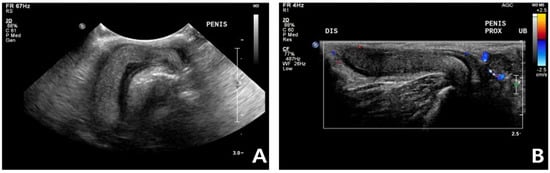

A general physical examination showed a persistent erection, and the penis was erect but not hard enough for penetration. The patient was slightly unsettled in the hospital and reacted aggressively to penis palpation. The surface of the penis was dry, and brown debris was detected at the glans (Figure 1). A soft movable mass (3.1 × 3.2 cm) was detected in the left inguinal area. Body temperature, measured rectally, was 38.9 °C and other vital parameters were within normal limits.

Figure 1. Non-ischemic priapism in a 14-year-old neutered male British shorthair. The penile tip is dry and shows a soft erection (A,B).